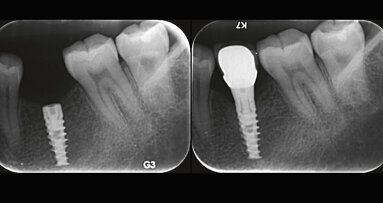

Several factors are involved in the achievement of implant primary stability, such as the insertion torque, the implant’s macrogeometry, the surgical technique, and the bone quality and quantity. Implant primary stability is considered one of the key factors for osseointegration and is associated with insertion torque. Several studies have suggested that insertion torque values of 25–45 N cm could prevent micromovements that could impair the bone healing around the implants. The aim of the present randomized clinical trial was to evaluate and compare the clinical outcome for implants placed with a high insertion torque (50–100 N cm) and a regular insertion torque (within 50 N cm) in healed ridges after two years.

Patients requiring implant therapy to replace missing teeth without the need for bone augmentation at the time of implant placement were selected for this study. All of the patients were divided according to a randomization list into two groups: high insertion torque (CT implants inserted with insertion torque ≥ 50 N cm) and regular insertion torque (Blossom CT implants with insertion torque < 50 N cm). The implants were left to heal submerged for three months and then restored with individualized abutments and cemented metal–ceramic crowns. Variables registered were insertion torque values, thickness of the buccal bone plate after implant osteotomy preparation, marginal bone level and facial soft-tissue level. All of the patients were followed for two years after implant placement, with recall visits at three, six, 12 and 24 months.

116 implants were placed: 58 implants were allocated to each group, with mean insertion torque ranging from 20 N cm to 50 N cm for regular insertion torque and from 50 N cm to 100 N cm for high insertion torque. Three implants failed. Two implants showed at the 12-months evaluation a marginal bone loss > 1.5 mm and were thus considered unsuccessful.

Implants inserted with a high insertion torque in healed bone ridges showed more periimplant bone remodeling and facial soft-tissue recession than implants inserted with regular insertion torque after two years, both in the maxilla and in the mandible. The findings suggest that the clinician should pay attention to several factors in implant therapy, such as the thickness of the buccal bone, the corticalization of the surgical site, the implant’s macrogeometry and the potential influence of insertion torque on implant therapy outcomes.